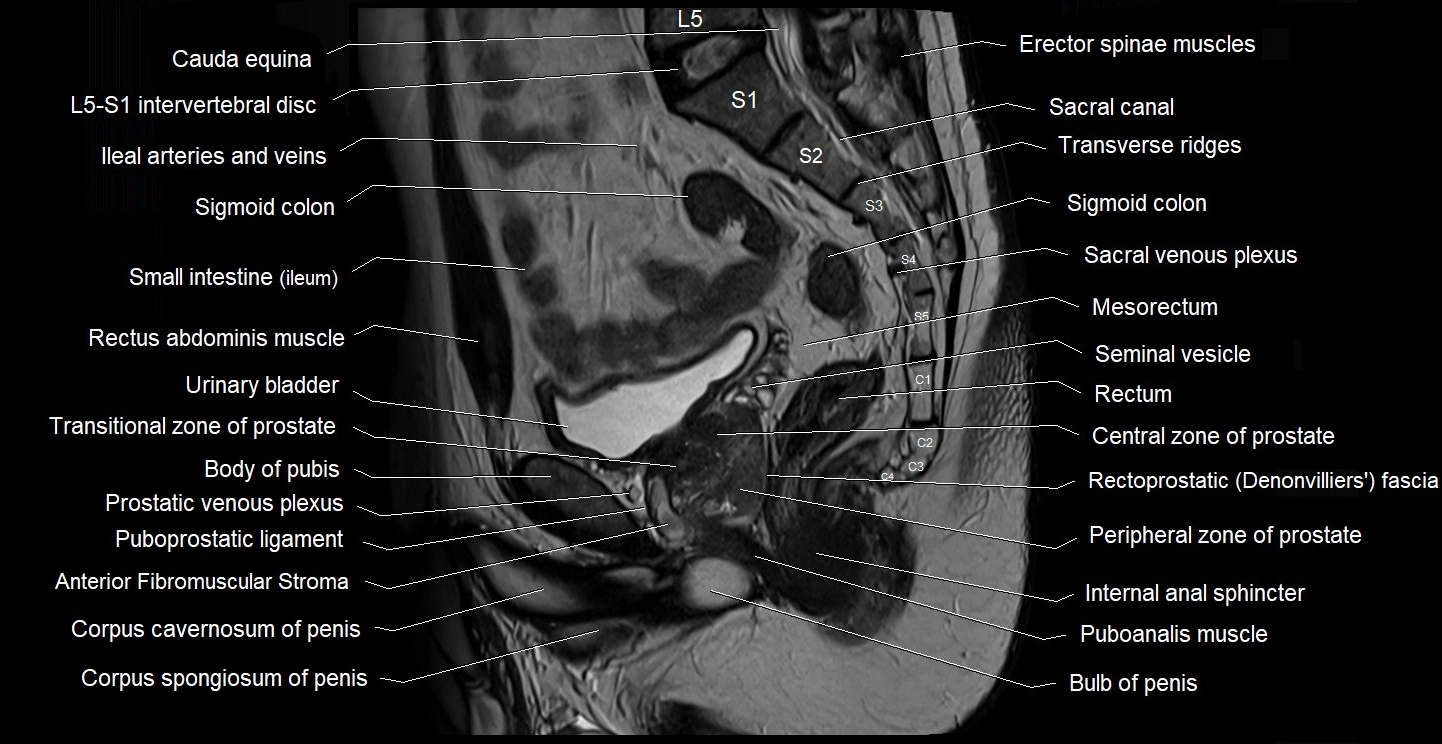

- Anterior Fibromuscular Stroma of prostate

- Body of pubis

- Bulb of Penis

- Bulbospongiosus muscle (Male)

- Central zone of prostate

- Internal anal sphincter

- Mesorectum

- Peripheral zone of prostate

- Puboanalis muscle

- Puboprostatic ligament

- Rectoprostatic fascia (Denonvilliers' fascia)

- Rectum

- Seminal vesicle

- Transitional zone of prostate